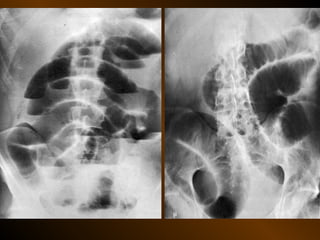

CĂNG GIÃN ỐNG TIÊU HÓA

PHÂN BIỆT

RUỘT NON – ĐẠI TRÀNG

• Các nếp Kerckring

• Nếp ngấn thanh mạc

• Khẩu kính

• Số lượng quai

• Phân bố các quai ruột

• Cao / rộng

• Chất cặn bã